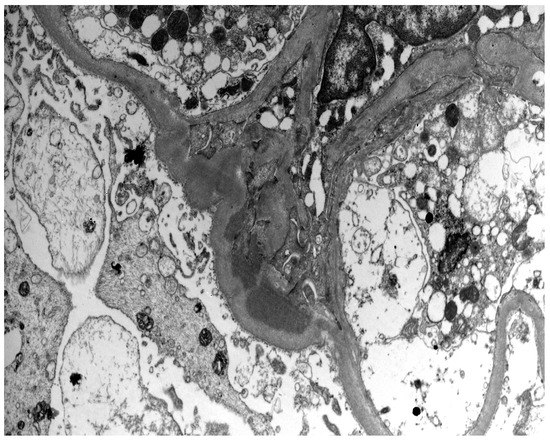

- Berger, J.; Hinglais, N. Intercapillary deposits of IgA-IgG. J. D’urologie Nephrol. 1968, 74, 694–695. [Google Scholar]

- Haas, M. Histologic subclassification of IgA nephropathy: A clinicopathologic study of 244 cases. Am. J. Kidney Dis. 1997, 29, 829–842. [Google Scholar] [CrossRef]

- Cattran, D.C.; Coppo, R.; Cook, H.T.; Feehally, J.; Roberts, I.S.D.; Troyanov, S.; Alpers, C.E.; Amore, A.; Barratt, J.; Berthoux, F.; et al. The Oxford classification of IgA nephropathy: Rationale, clinicopathological correlations, and classification. Kidney Int. 2009, 76, 534–545. [Google Scholar] [CrossRef] [PubMed]

- Roberts, I.S.D.; Cook, H.T.; Troyanov, S.; Alpers, C.E.; Amore, A.; Barratt, J.; Berthoux, F.; Bonsib, S.; Bruijn, J.A.; Cattran, D.C.; et al. The Oxford classification of IgA nephropathy: Pathology definitions, correlations, and reproducibility. Kidney Int. 2009, 76, 546–556. [Google Scholar] [CrossRef] [PubMed]

- Jennette, J.C.; Olson, J.L.; Silva, F.G.; D’Agati, V.D. Heptinstall’ s Pathology of the Kidney, 7th ed.; LWW: Philadelphia, PA, USA, 2015. [Google Scholar]